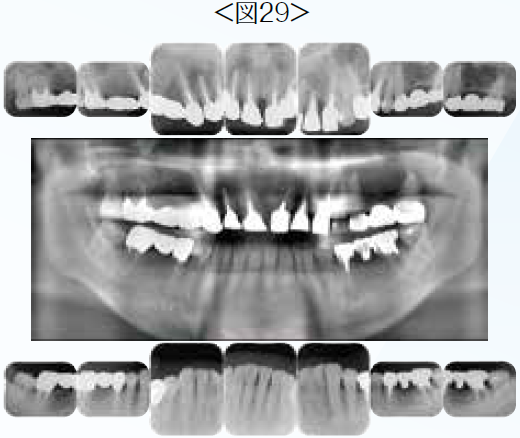

上顎はほぼ全額にわたり補綴処置がなされており無髄歯も多数認められた。欠損部にはロングスパンのブリッジが装着され、支台歯の負担過重が予測された。症例2のように個々の歯の評価と咬合再構成を行うにあたり機能を回復し、長期的な予後の安定にはインプラントを用いた治療の方が有利であると判断した。インプラントを用いた補綴設計で、できる限りシンプルな設計になるよう考慮した結果、上顎の歯は全て抜歯しインプラントによる補綴を選択。下顎に関しては上下の顎間関係がⅢ級傾向を示し天然歯の位置で補綴処置を行った場合、交差咬合になるリスクがあったため、後方臼歯は抜歯してインプラントによる咬合回復を計画した。口腔内スキャンのデータとCBCTのデータをマッチングし、インプラントポジションを最終補綴のデザインから外科的に問題なく補綴形態に支障の出ない位置に決定をした。全ての治療計画・補綴設計が決定したのちに患者に説明し、同意を得たので治療を開始した。インプラント埋入には全てサージカルガイドを利用し、術前に計画したインプラントポジションに極力合わせるように努めた。プロビジョナル・レストレーションを装着し、審美的・機能的・構造的・生物学的に問題ないことを確認したのち最終補綴装置を装着した。サージカルガイドを用いてインプラントを埋入したことで、最初の術前の補綴デザインと大きく変わることなく補綴装置を装着できた。術後間もない症例であるため、これからはメンテナンスを通じて口腔内の機能安定が維持されていることを引き続き管理していきたい。(図28~図36)